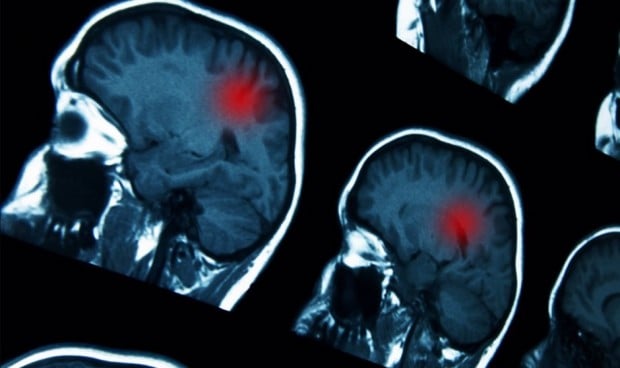

Un equipo de investigación del Daegu Gyeongbuk Institute of Science and Technology (Corea del Sur) ha descubierto una nueva mutación genética relacionada con la discapacidad intelectual y ha identificado un mecanismo de señalización de activación sináptica excitatoria relacionado con la mutación. Se espera que el descubrimiento, publicado en la revista científica 'Nature Communications', presente una nueva dirección de investigación para el tratamiento de los trastornos del desarrollo del cerebro mediante la coordinación de la actividad de señalización sináptica excitatoria.

Una sinapsis es un canal especial que transmite información neuronal de forma rápida y precisa, y controla todas las funciones cerebrales. Las sinapsis se dividen en sinapsis excitatorias y sinapsis inhibitorias. Estas sinapsis cooperan entre sí para que las funciones cerebrales funcionen con normalidad y mantengan el equilibrio de la red de circuitos neuronales. Se sabe que diversas enfermedades del desarrollo cerebral, enfermedades mentales, enfermedades cerebrales degenerativas, etc. se producen cuando se altera este equilibrio.